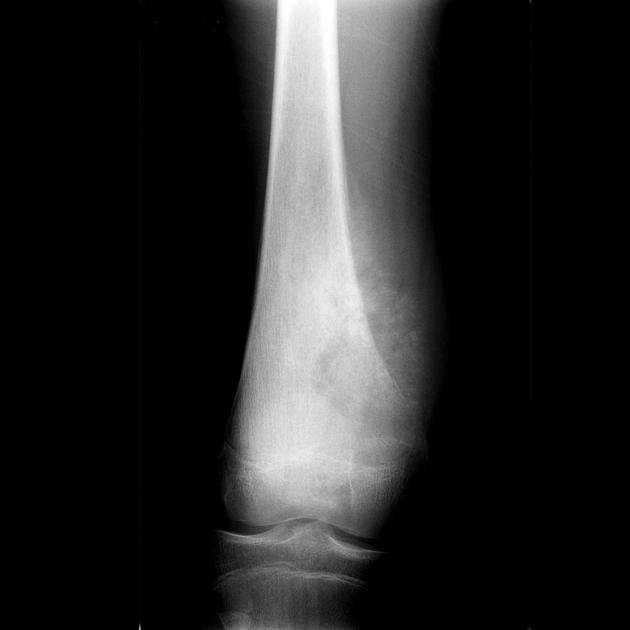

Sunburst (spiculated — radial) Fine radiating spicules of new bone projecting perpendicularly from the cortical surface in a radial pattern resembling the rays of the sun; the spicules radiate outward from the periosteum into the soft tissues; they represent new bone deposited along the Sharpey`s fibres and along the vessels penetrating the periosteum perpendicularly; the spicules are thin, irregular, and often widely spaced AGGRESSIVE — classically associated with osteosarcoma; the sunburst pattern indicates rapid periosteal elevation and bone formation by a highly aggressive process; the tumour is growing so rapidly that it forces the periosteum outward faster than organised layered bone can be deposited, and instead precipitates bone along the perpendicular periosteal vessels and fibres Osteosarcoma (the classic cause — the `sunburst` periosteal reaction is virtually pathognomonic of high-grade osteosarcoma); aggressive metastases (rare); occasionally in very aggressive osteomyelitis The sunburst periosteal reaction is one of the most specific radiological signs in musculoskeletal oncology; when seen in a child or adolescent in the metaphysis of a long bone — it should be considered high-grade osteosarcoma until proven otherwise; osteosarcoma classically occurs at the knee (distal femur 40%, proximal tibia 20%) in adolescents; the sunburst pattern is also important to recognise in hemangiomas of bone (but the spicules are coarser — the `corduroy cloth` appearance on AP radiograph)

Primary Malignant Tumours Osteosarcoma; Ewing`s sarcoma; chondrosarcoma (periosteal); parosteal osteosarcoma; periosteal osteosarcoma; lymphoma of bone; multiple myeloma (rarely) Osteosarcoma: sunburst ± Codman`s triangle; Ewing`s sarcoma: onion-skin (laminated) ± Codman`s triangle; periosteal osteosarcoma: spiculated periosteal reaction on the cortical surface without medullary involvement; parosteal osteosarcoma: dense, lobulated periosteal mass attached to the cortex without medullary invasion Age distribution is critical: osteosarcoma peak 10–20 years; Ewing`s sarcoma 5–30 years (peak 10–20 years); chondrosarcoma and lymphoma in adults; parosteal osteosarcoma typically 20–40 years; location: osteosarcoma = metaphysis of long bones (distal femur 40%); Ewing`s sarcoma = diaphysis (tibial and femoral shaft) and flat bones (pelvis, ribs, scapula) — `any bone any age`

• Sunburst periosteal reaction: radially diverging spicules of new bone perpendicular to the cortex; the periosteum is elevated so rapidly that bone is deposited along the perpendicular periosteal vessels (Haversian canals and Volkmann canals) and along the Sharpey`s fibre tracts; virtually pathognomonic of high-grade osteosarcoma in a child or adolescent; also produced by aggressive metastases and occasionally by aggressive osteomyelitis; the spicules are thin and irregular (unlike the thick coarse spicules of periosteal haemangioma)

• Sunburst = osteosarcoma (until proven otherwise): sunburst periosteal reaction in a child/adolescent in the metaphysis of a long bone = high-grade osteosarcoma; the most specific aggressive periosteal sign for osteosarcoma; also seen in very aggressive metastatic disease but this is rare in children